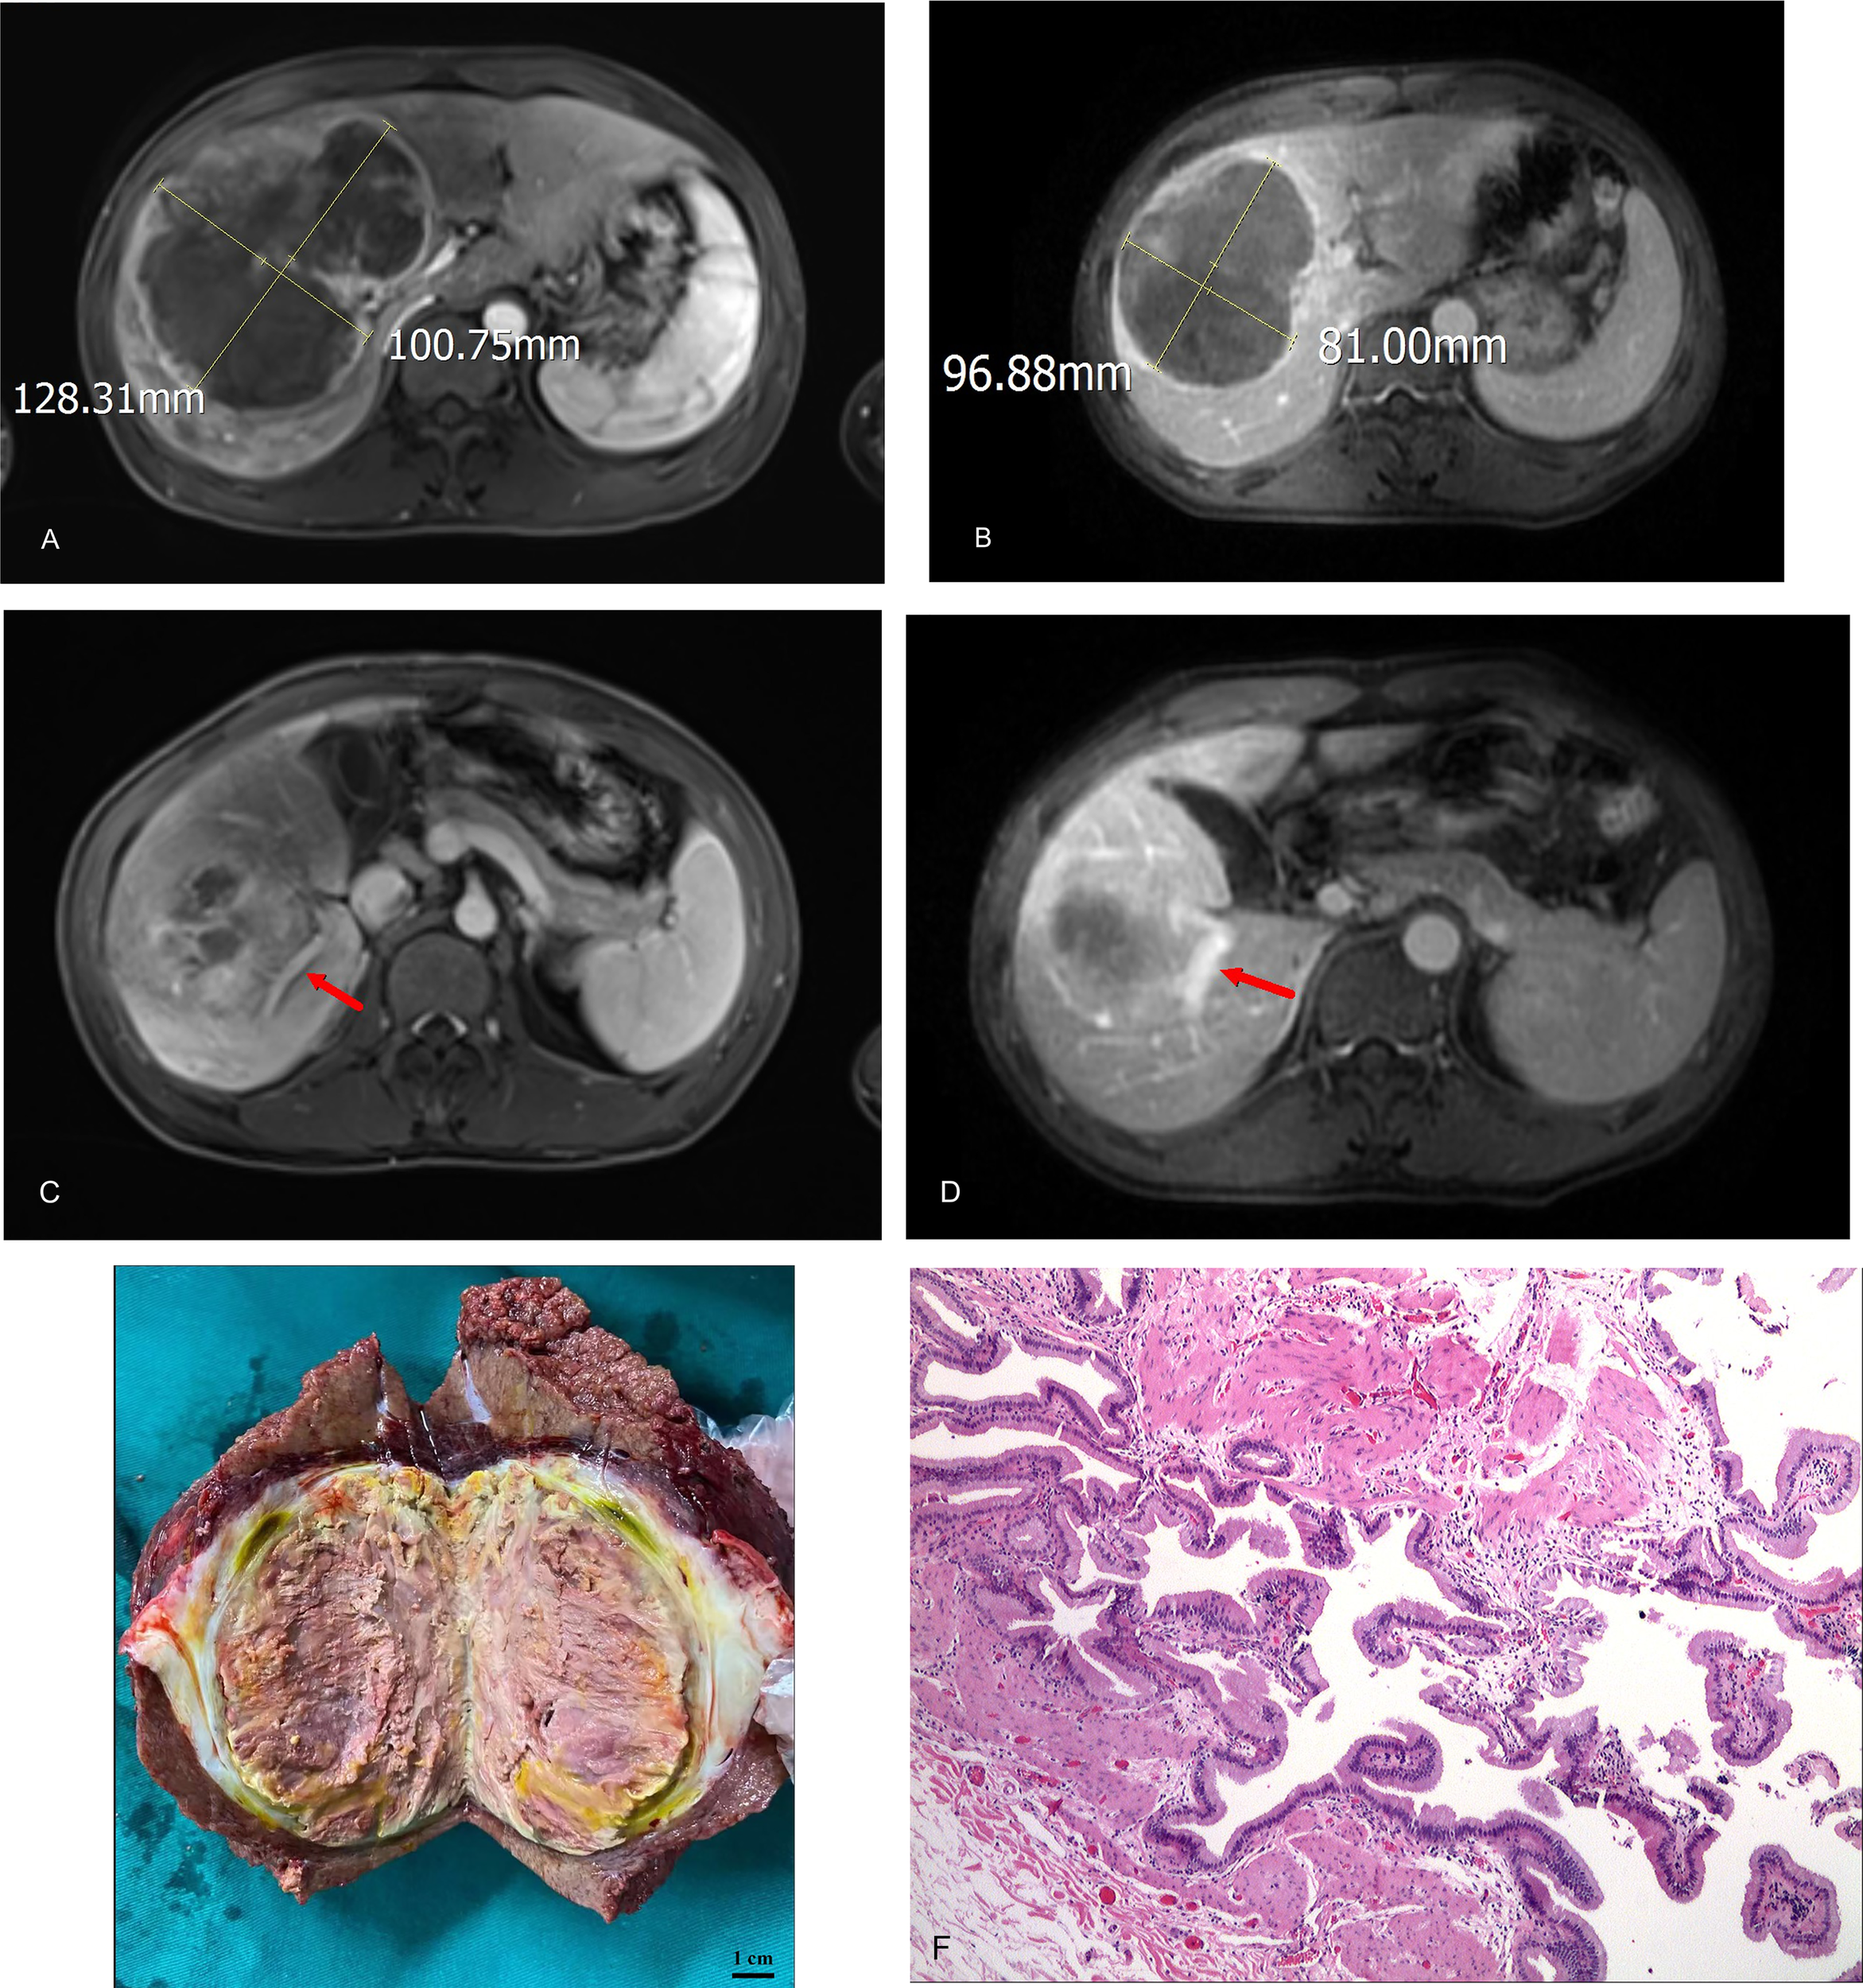

A patient with BCLC stage B whose preoperative enhanced MRI indicated a huge occupation in the middle liver lobe with involvement of the right portal vein and the right hepatic vein was initially diagnosed with hepatocellular carcinoma. After 6 cycles of therapies, the tumor responded well and shrank significantly, and level of AFP decreased from 410,302 ng/ml to 13.9 ng/ml. After the joint consultation of the multi-disciplinary treatment, it was decided to perform mid-liver tumor resection and cholecystectomy. Postoperative pathology showed a large area of tumor cell necrosis and a small amount of tumor cell remnants which was considered as pathological complete response (pCR), 2 patients reached partial response (PR) (Figure 2). 7 cases had stable disease (SD), and 9 cases showed progressive disease (PD) (Table 3). The median disease-free survival was 7.4 months, and the median overall survival could not be assessed at the moment (Figure 3). ORR and DCR was 15.0%, 50.0% respectively.

Figure 2

(A) initial tumor size (portal vein phase); (B) post-treatment/pre-operative tumor size (portal vein phase); (C) portal vein involvement(pre-treatment); (D) portal vein involvement (post-treatment/pre-operative); (E) Tumor specimens; (F) Pathological images (200X).